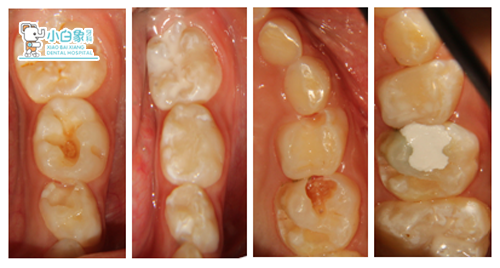

65邻合面龋坏达牙本质深层,探诊(+),温度测试疼痛,牙龈无红肿。

64邻合面龋坏达牙本质浅层,探诊(-),温度测试同正常牙。

65去腐质,疼痛,间接封慢失。

64 74 75 去腐质,备洞,隔湿干燥,纳米充填及纳米封闭,调合。

36去腐质,备洞,隔湿干燥,科尔树脂充填及合面纳米封闭,调合。